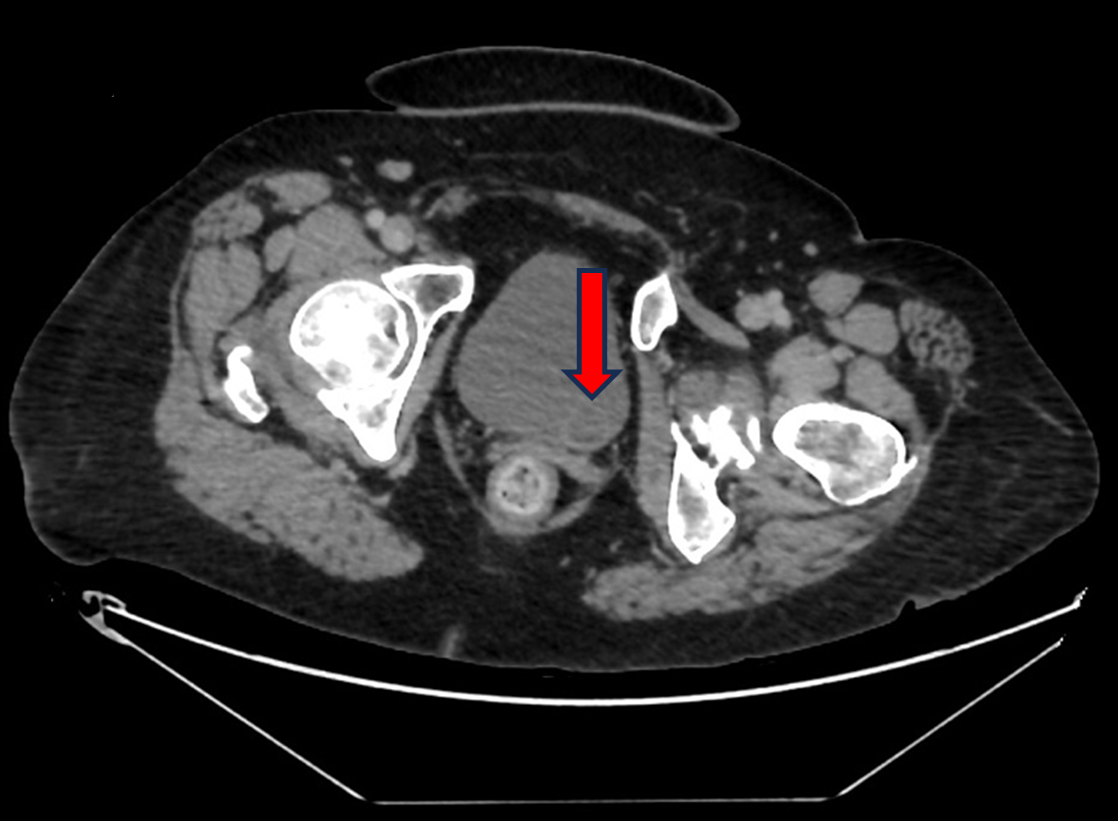

Surgery after near complete response to combined immunotherapy and tyrosine kinase inhibitor therapy for metastatic renal cell carcinoma with inferior vena cava tumour thrombus